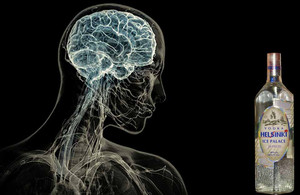

В наши дни такое печальное явление, как алкоголизм, все чаще подчеркнуто указывает на половую принадлежность- \"женский\". Проблема развивается столь стремительно, что статистические данные повергают в шок и начинаешь осознавать, сколько погибших судеб, разбитых семей и брошенных на произвол детей стоит за этой трагедией. Как быть? Что делать? Ответы на все самые распространенные вопросы связанные с проблемой женского алкоголизма даст известный гипнолог Геннадий Гончаров, который уже более 20 лет занимается лечение алкоголизма нетрадиционными методами. Почему считается, что женский алкоголизм неизлечим? Алкоголизм наносит большой вред личности, люди становятся неадекватными. Разовый прием алкоголя ведет к гибели клеток мозга: неважно, что это - дешевое пиво или дорогой коньяк. Высчитывается количество спирта, формальдегид, который вырабатывается и является ядом - это и влияет на мозг. Человек должен понимать, что любой